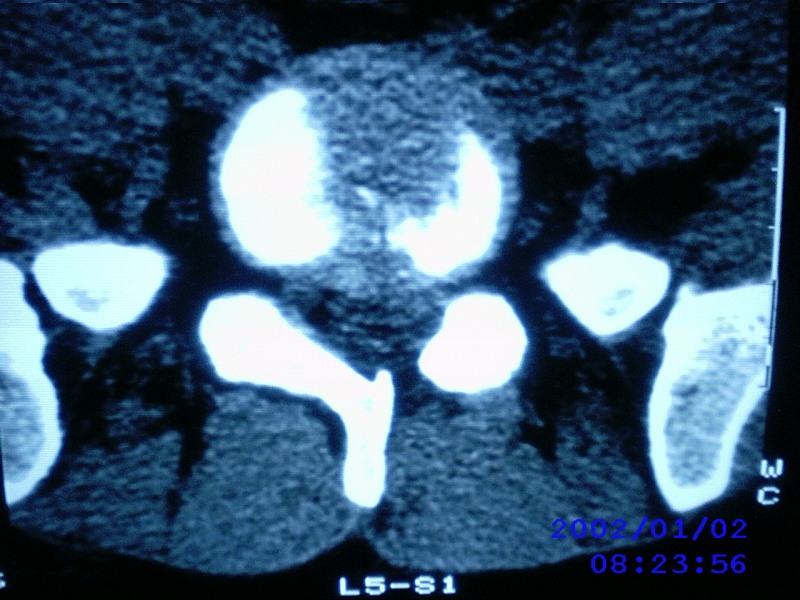

患者,男性,40岁,腰痛伴左下肢疼痛、麻木6年。5年前做过腰椎间盘手术,具体是哪个位置病人记不清了。

我拍的是l4-5、l5-s1

1)l4/5及l5/s1左侧椎板术后改变。2)l5/s1椎间盘突出,l5椎体下缘许莫氏结节。3)l4/5椎间盘膨出并突出。4)l3/4椎间盘膨出。

1)l4/5及l5/s1左侧椎板术后改变。2)l5/s1椎间盘突出,l5椎体下缘许莫氏结节。3)l4/5椎间盘膨出并突出。

1)l4/5及l5/s1左侧椎板术后改变。2)l5/s1椎间盘突出,l5椎体下缘许莫氏结节。3)l4/5椎间盘膨出并突出。4)l3/4椎间盘膨出。支持!